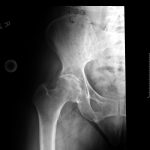

A 62-year-old African American male weighing 185lbs diagnosed with osteo/degenerative arthritis received Advita’s Alte on Neck Preserving stem with a Biolox® delta femoral head and InteGrip® acetabular shell. The patient underwent general anesthesia using a direct anterior surgical approach with an incision size of 9cm. There was an estimated blood loss of 200cc and surgery duration was 30minutes. The patient was discharged the same day as the operation with a walker to in home care for rehabilitation.

Pre-Op AP Pelvis

Harris Hip Score 48 (max=100) | Oxford Hip Score 19 (max=48)

6-Week Post-Op

Harris Hip Score 96 (max=100) | Oxford Hip Score 38 (max=48)

3-Month Post-Op

Harris Hip Score 89 (max=100) | Oxford Hip Score 44 (max=48)

1-Year Post-Op

Harris Hip Score 96 (max=100) | Oxford Hip Score 46 (max=48)

CONCLUSION

This patient presented with low Harris Hip and Oxford Hip scores before his total hip replacement. The direct anterior approach, which was used in this surgery, has been associated with faster functional recovery than the posterolateral approach. One year after surgery, his Harris Hip score increased by more than 50.0 percent, and his Oxford Hip score increased by more than 58.7 percent. The outcomes of his surgery continue to be followed each year, and the patient is satisfied with his total hip replacement. •